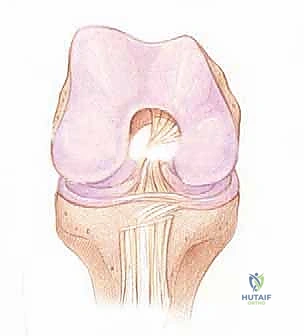

يقع الرباط الصليبي الأمامي في قلب مفصل الركبة، ويمتد بشكل مائل من الشق بين اللقمتين (Intercondylar notch) في عظم الفخذ، نزولاً إلى السطح العلوي لعظم الظنبوب (القصبة).

الحزم التشريحية (Anatomical Bundles)

من الناحية الوظيفية والتشريحية، لا يعمل الرباط كوحدة واحدة، بل ينقسم إلى حزمتين رئيسيتين تعملان بتناغم عجيب:

1. الحزمة الأمامية الإنسية (Anteromedial Bundle - AM): هذه الحزمة تكون مشدودة بشكل رئيسي عندما تكون الركبة في وضعية الانثناء (Flexion). وظيفتها الأساسية هي منع عظم القصبة من الانزلاق للأمام بعيداً عن عظم الفخذ.

2. الحزمة الخلفية الوحشية (Posterolateral Bundle - PL): تكون هذه الحزمة مشدودة عندما تكون الركبة في وضعية الاستقامة الكاملة (Extension). هذه الحزمة هي المسؤولة الأولى عن توفير الثبات الدوراني للركبة، وهي التي تمنع الركبة من الالتواء أثناء تغيير الاتجاه المفاجئ.